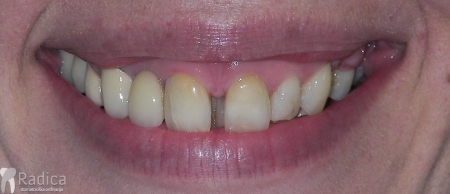

Na sljedećoj slici mogu se vidjeti početak i kraj ortodontske terapije. Pacijentica je upućena od svog stomatologa nakon što nije bila zadovoljna izgledom osmjeha i odnosom zuba i gingive u privremenom protetskom radu. Napravljena je ortodontska terapija samo u gornjoj čeljusti a nakon toga novi privremeni protetski rad.